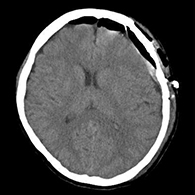

脳梗塞の原因となる頚動脈狭窄症に対して内膜剥離術を行う

56歳男性、左半身麻痺で発症した。

<術前画像所見>

右側で頸部内頚動脈が細くなっているため右脳に脳梗塞を生じた。

<術後画像所見>

頸部狭窄は解消しており、新たな脳梗塞など生じていない。